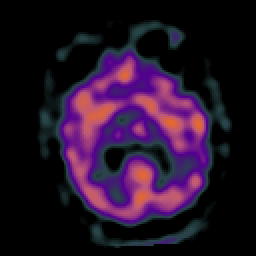

Subacute Stroke, overlay -- Slice #14

[Home][Help][Clinical] Slice 14